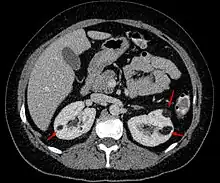

Angiomyolipoma in both kidneys (arrows) in computer tomography. The tumours are hypodense (dark) due to fat content. | |

Three methods of scanning can detect angiomyolipomas: ultrasound, computed tomography (CT), and magnetic resonance imaging (MRI).[5] Ultrasound is standard and is particularly sensitive to the fat in angiomyolipomas, but less so to the solid components. However, accurate measurements are hard to make with ultrasound, particularly if the angiomyolipoma is near the surface of the kidney (grade III).[4] CT is very detailed and fast, and allows accurate measurement. However, it exposes the patient to radiation and the dangers that a contrast dye used to aid the scanning may itself harm the kidneys. MRI is safer than CT, but many patients (particularly those with the learning difficulties or behavioural problems found in tuberous sclerosis) require sedation or general anaesthesia, and the scan cannot be performed quickly.[3] Some other kidney tumours contain fat, so the presence of fat is not diagnostic. Distinguishing a fat-poor angiomyolipoma from a renal cell carcinoma (RCC) can be difficult.[6] Both minimal fat AMLs and 80% of the clear-cell type of RCCs display signal drop on an out-of-phase MRI sequence compared to in-phase.[7] Thus, a lesion growing at greater than 5 mm per year may warrant a biopsy for diagnosis.[3]